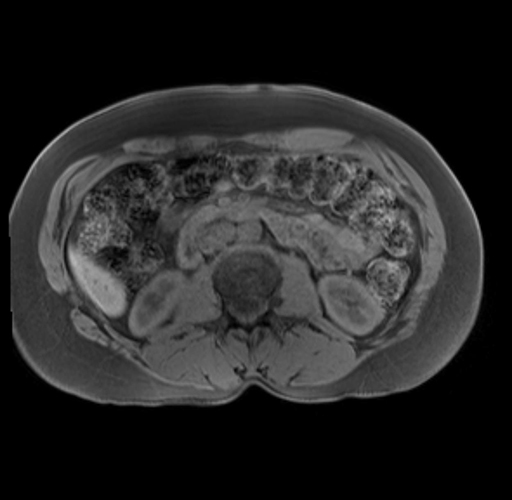

Imaging Analysis

Look through the patient's CT scan to identify any areas of concern for the necessary procedure.

Based on your CT findings, which issue(s) are present and would give reason for "planned slowing down moment(s)" in this case?